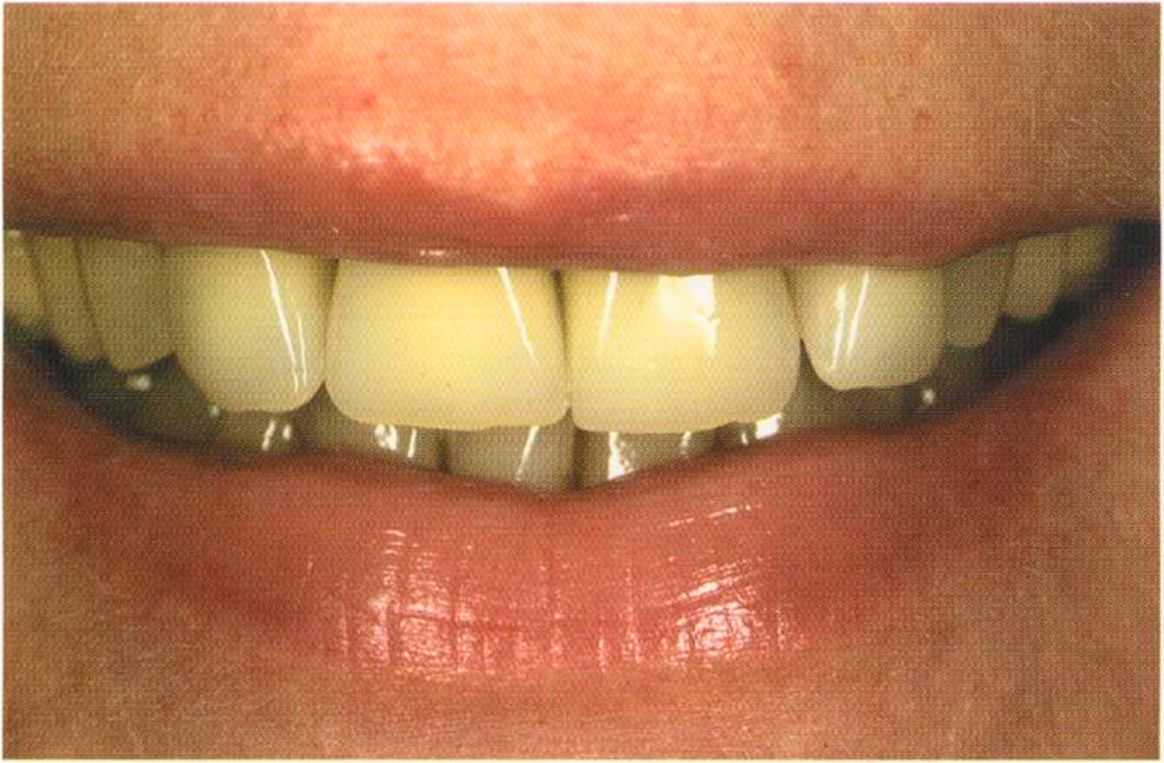

Эта женщина пришла в клинику доктора Лангханке с металлокерамической реставрацией.

Ей не нравились типичные в таких случаях темные края коронок и опаковость керамики.

Окончательный результат и естественный цвет губ. Женщина была очень счастлива и довольна своим новым внешним видом. Наконец мечта осуществилась — нет больше этих щелей на видимом участке. Всей нашей команде было очень приятно видеть радость в ее глазах.